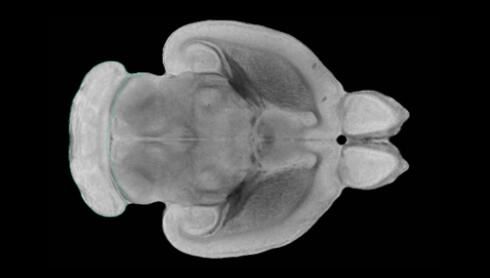

隨著機(jī)體年齡增加,肌肉和關(guān)節(jié)都會變得僵硬,這就會使得日?;顒幼兊酶永щy,本文研究表明,我們的大腦也是如此,與年齡相關(guān)的大腦僵硬對大腦干細(xì)胞的功能或許有著重要影響。文章中,研究人員對年輕和老化大鼠的大腦進(jìn)行研究闡明了年齡相關(guān)大腦僵硬對少突膠質(zhì)前體細(xì)胞(OPCs,oligodendrocyte progenitor cells)功能的影響。OPCs是一類對維持正常大腦功能非常重要的大腦干細(xì)胞,其對于髓磷脂的再生也非常重要,髓磷脂是神經(jīng)組織周圍的脂肪鞘,在多發(fā)性硬化癥中髓磷脂的再生常常會被損傷,機(jī)體老化對這些細(xì)胞的影響常常會誘發(fā)多發(fā)性硬化癥的發(fā)生,這些細(xì)胞的功能在老化的健康人群中同樣會下降。

為了確定老化OPCs的功能缺失是否可以被逆轉(zhuǎn),研究人員將來自老化大鼠機(jī)體的老化OPCs轉(zhuǎn)移到了年輕大鼠柔軟的海綿狀大腦組織中去,值得注意的是,這些老化的大腦細(xì)胞能夠重新恢復(fù)活力,其行為非常像年輕更加強(qiáng)壯的細(xì)胞。這項研究中,研究人員在實驗室中開發(fā)出了具有可變僵硬程度的新型材料,并在受控環(huán)境下研究這些材料的生長及其對大鼠大腦干細(xì)胞的影響,這些材料能被工程化改造具有和年齡或老化大腦相似的柔軟程度。